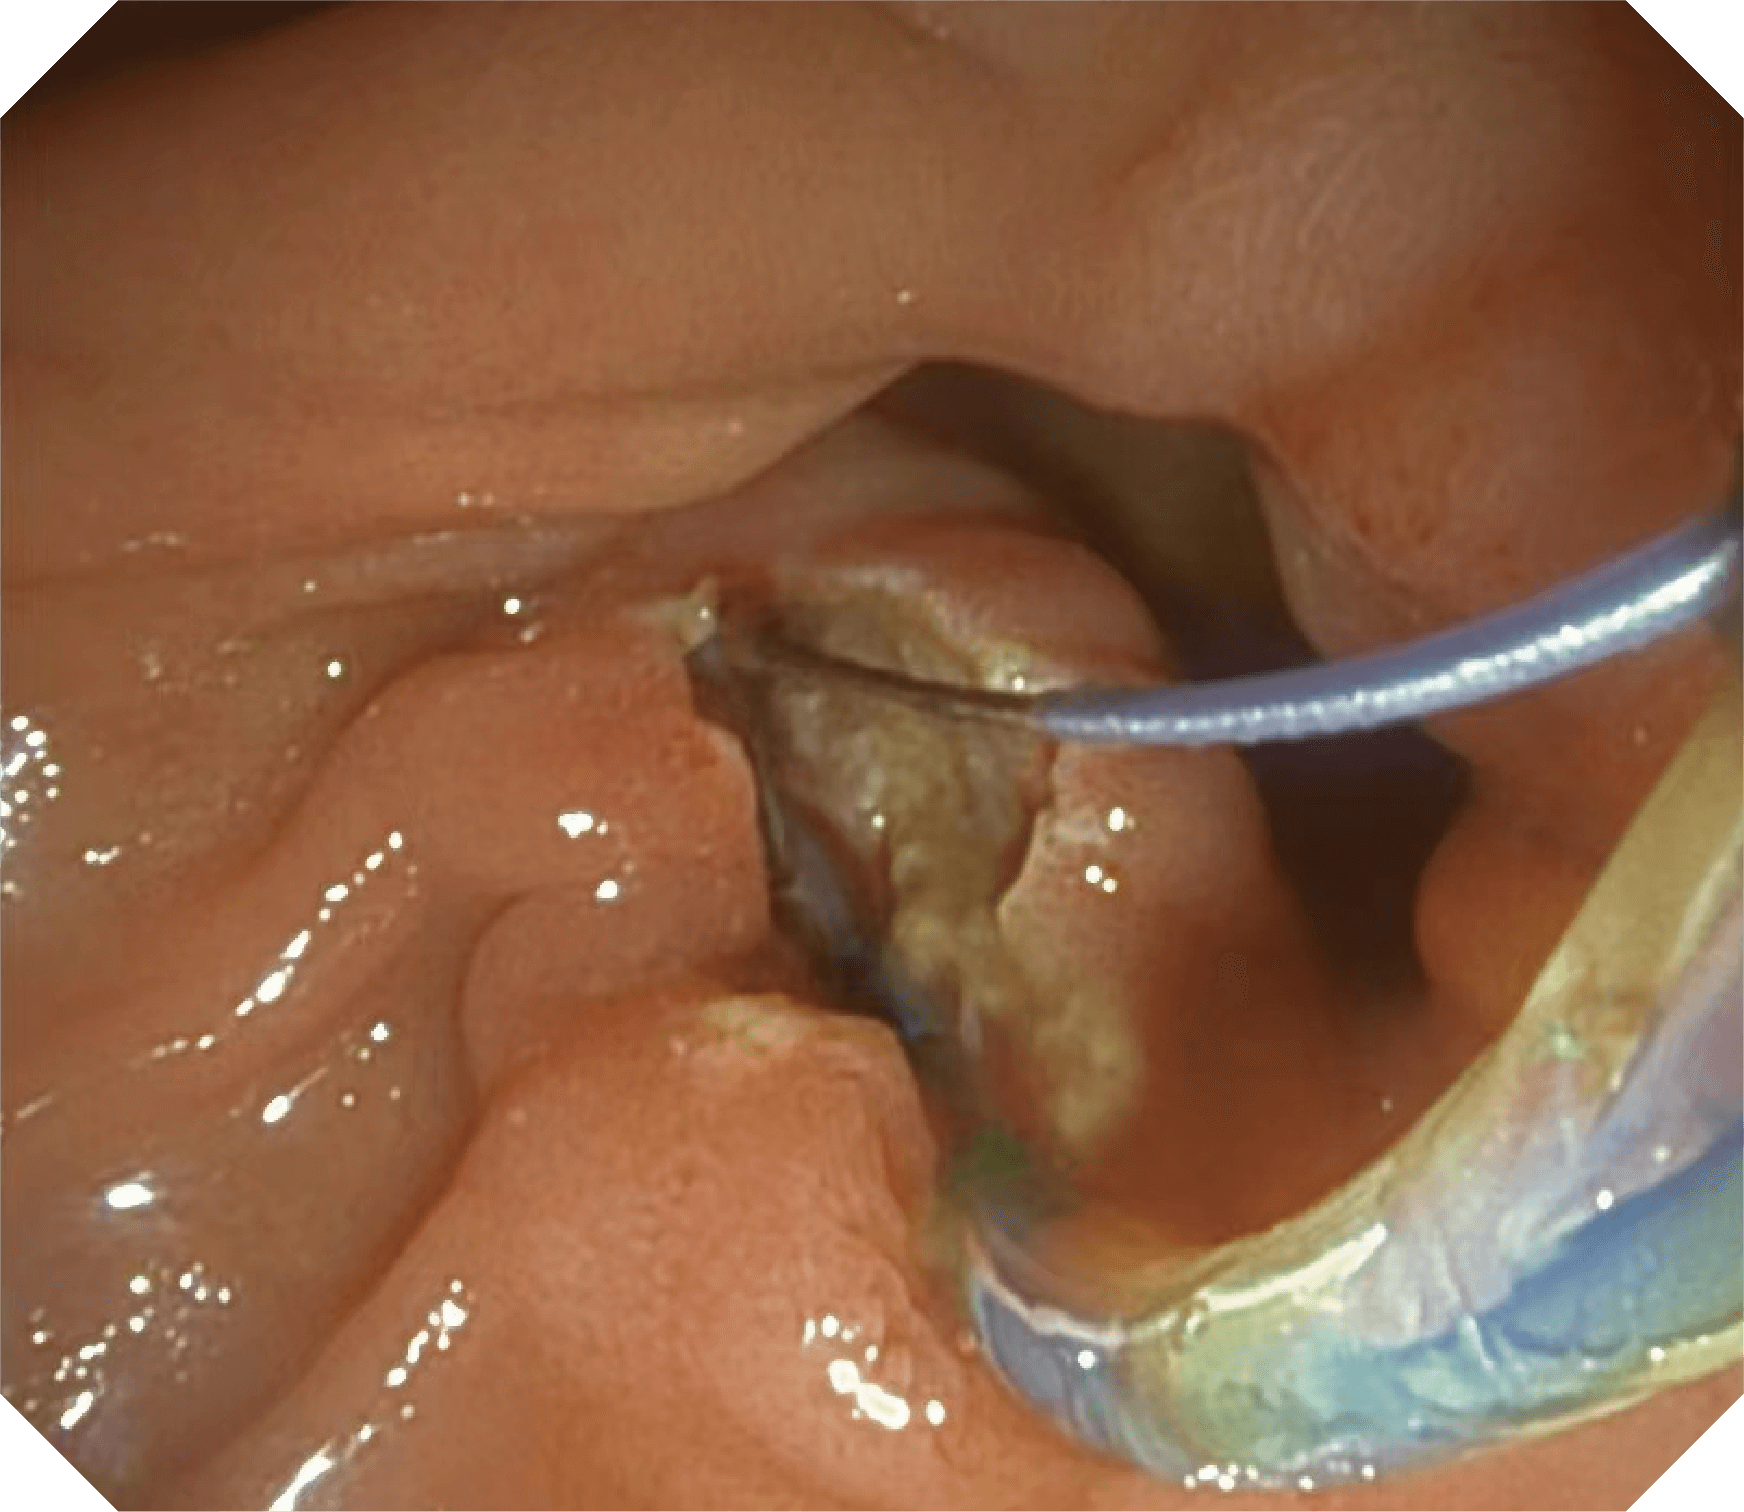

CMOS传感器提供高清内镜视野 SFI/VIST光学染色技术凸显病变区域

4.2mm大钳道,器械交换更顺畅

导丝机械锁紧功能

V槽设计提升导丝控制

优异的手术器械抬举性

更好的通过性,更稳定的镜体支撑力